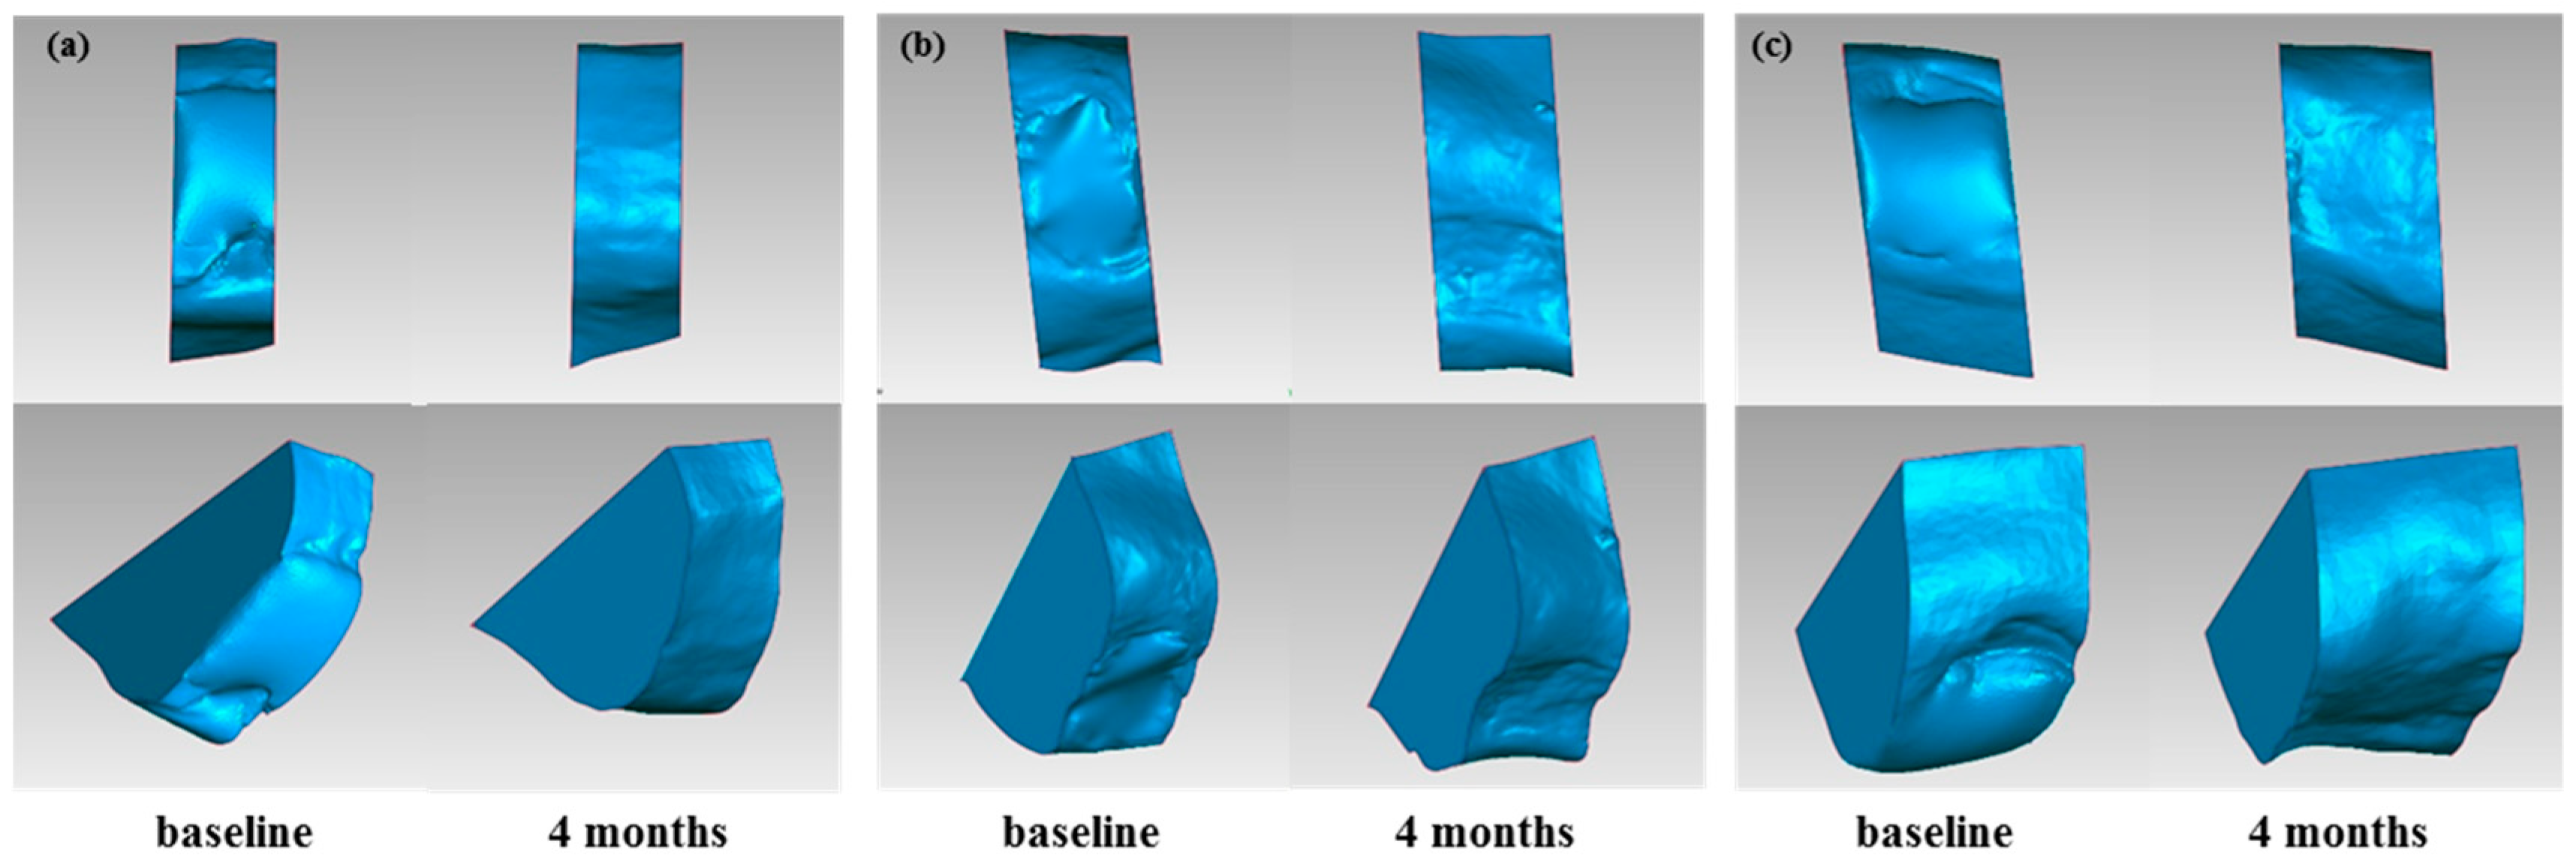

2.6. Volumetric Assessment of Soft and Hard Tissue

2.6.1. Volume Calculation for Soft Tissue/Stone Cast Measurement

3.2. Results of Volumetric Analysis